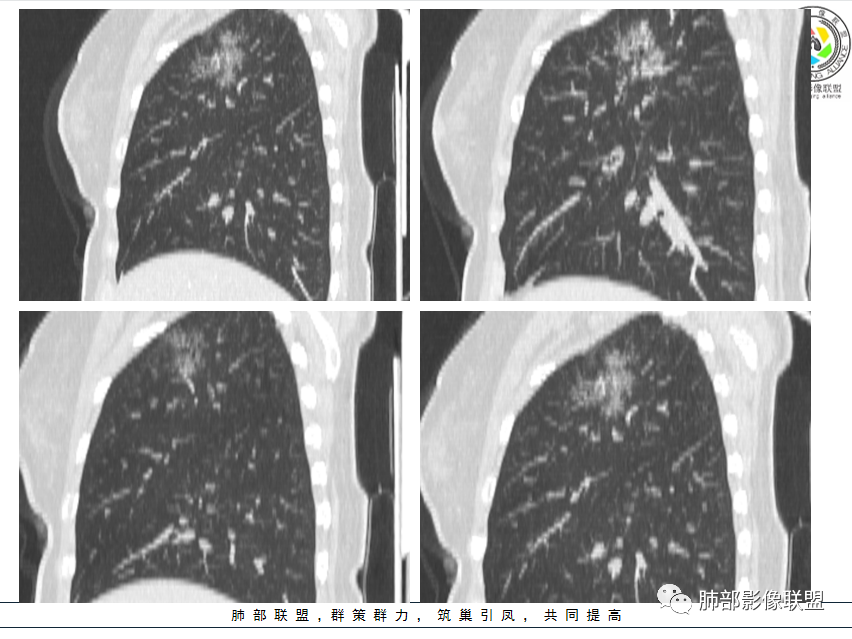

影像特点:右肺上叶混合磨玻璃影,边界清晰,结构松散,内有多结节堆积及支气管扩张影,可见小叶间隔增厚,并局部增厚的小叶间隔上亦存在微结节,胸膜侧可见纤细索条,病灶周围可见多发微结节影。

总体分析:从病灶分布来看符合结核的好发位置,影像表现也符合结核的多态性,且出现卫星灶。由于有边界清晰的GGO,需要鉴别腺癌,虽然此病例有边界清晰的GGO,但是它的GGO的边缘有结节感,呈多结节堆积,而腺癌的GGO缺乏这种“多结节堆积感”,另外,此病例也没有发现腺癌的胸膜凹陷征、毛刺征及月牙铲等。

间质性肺结核是结核的一种特殊影像学表现,为继发性肺结核,影像学表现与常见的继发性肺结核有所不同,有一定的特征性。

1、年轻人多见,一般提示免疫力可能有下降。 2、好发部位与其它结核类似,上叶及下叶背段为主。 3、烟花征,反晕征,环呈结节状,可以伴随空洞,树芽征,结节灶,胸水。(反晕征:一般周围实性环形高密度影,中央丛密度低;一般环超过圆的3/4,结核的环主要是小叶核心结节组成,类似于多发树芽征聚集,边缘结节感。中央的晕:可以是腺泡结节,树芽征,细网状,磨玻璃影,很少正常,主要成分是小叶内间质增厚、小叶核心结节、肺泡内病变。)其实也体现了结核的多灶性、多态性特点。

4、其实不一定完全表现为反晕征,还有比较密集的烟花,聚集成团,与反晕征同在。